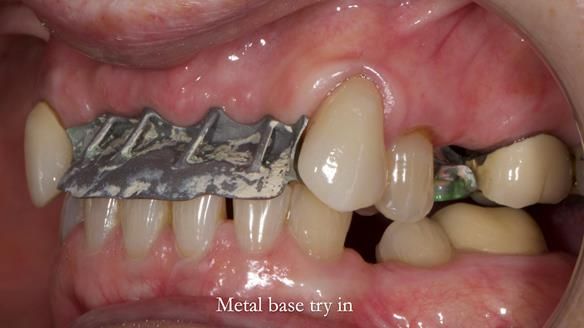

- Metalwork framework try-in – to verify fit, path of insertion, and support.